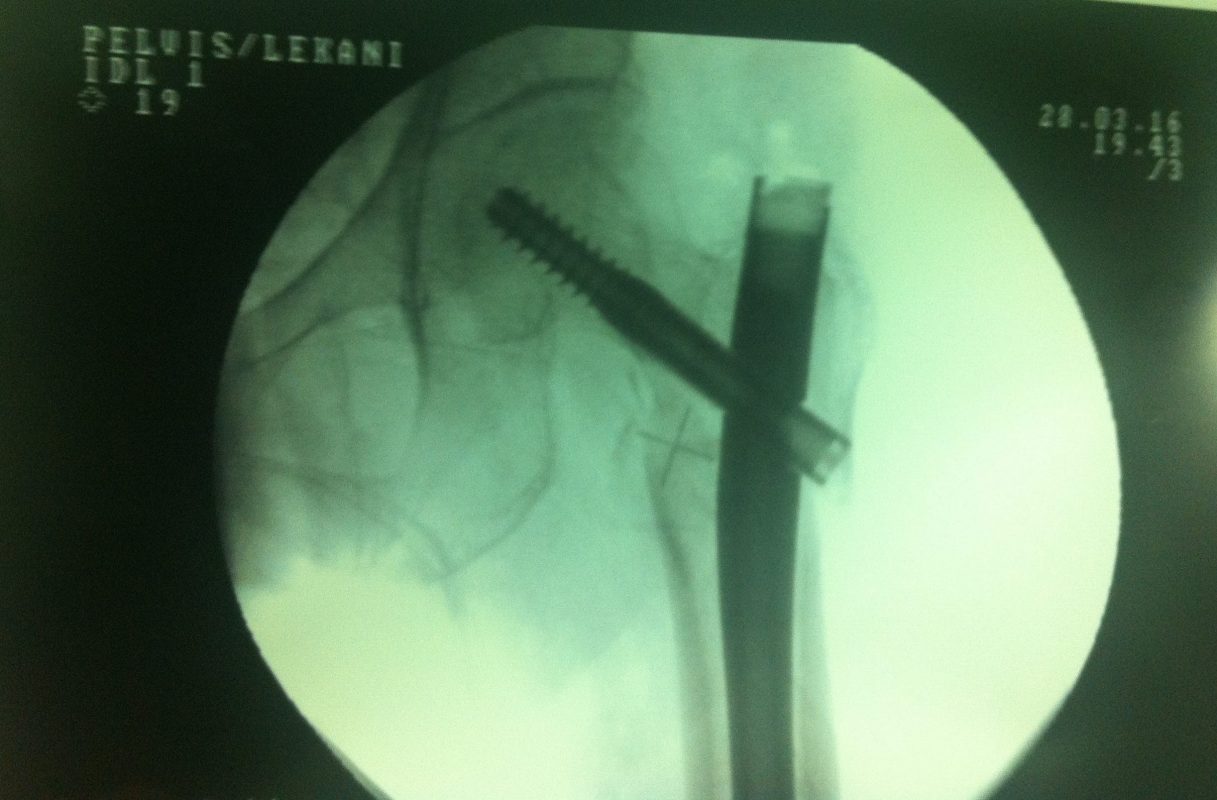

Υποκεφαλικό : Είναι ενδαρθρικό κάταγμα στον αυχένα του μηριαίου (το εσωτερικό του αρθρικού θυλάκου), το οποίο διακόπτει την αιμάτωση της κεφαλής του μηριαίου και οδηγεί σε μη πόρωση του κατάγματος (ΟΣΤΕΟΝΕΚΡΩΣΗ της Μηριαίας κεφαλής). Σε ασθενείς κάτω των 65 ετών αντιμετωπίζεται χειρουργικά με κοχλίωση στις πρώτες 12 ώρες. Τρείς βίδες σε σχήμα Τ με την βοήθεια τηλεόρασης διαδερμικά χωρίς διάνοιξη. Σε ασθενείς από 65-75 ετών γίνεται ολική αρθροπλαστική και σε ασθενείς άνω των 75 ετών αλλάζεται μόνο η κεφαλή χωρίς την αλλαγή της κοτύλης. Ο ασθενής περπατάει άμεσα μετεγχειρητικά στις 5 ώρες και εξέρχεται από το νοσοκομείο σε 1 -2 ημέρες. Στην κοχλίωση μπορεί να εξέλθει και την ίδια ημέρα.